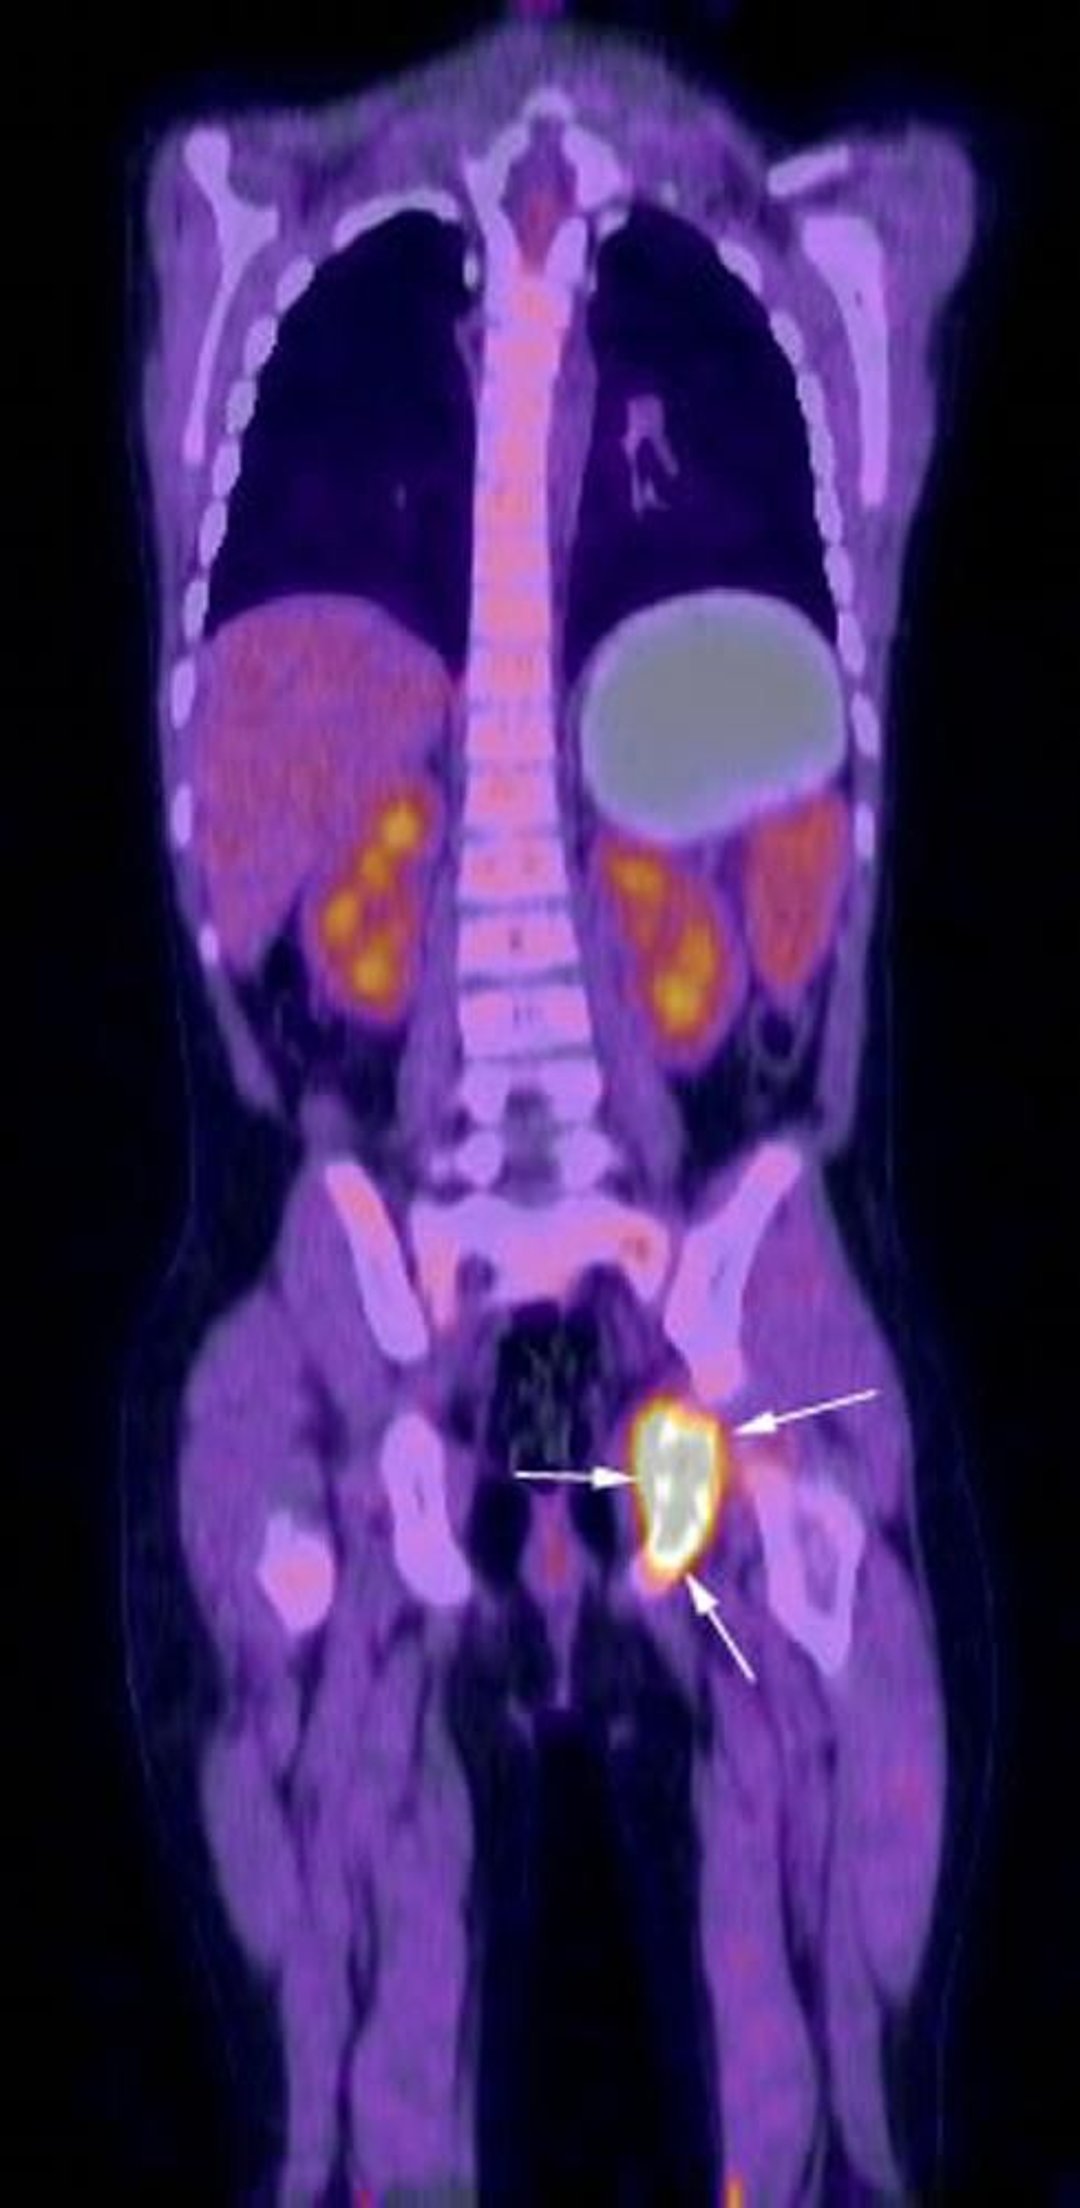

PET-TC con fluoro-desossiglucosio

L'immagine di ricostruzione coronale dell'esame PET-TC con fluoro-desossiglucosio mostra un'intensa attività metabolica nella regione dell'ischio sinistro (frecce) corrispondente all'istiocitosi a cellule di Langerhans già diagnosticata al paziente.

Image courtesy of Hakan Ilaslan, MD.